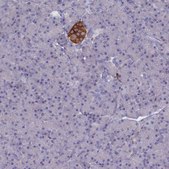

HPA044637

Anti-GAD2(GAD67) Antibody

immunohistochemistry: 1:200-1:500